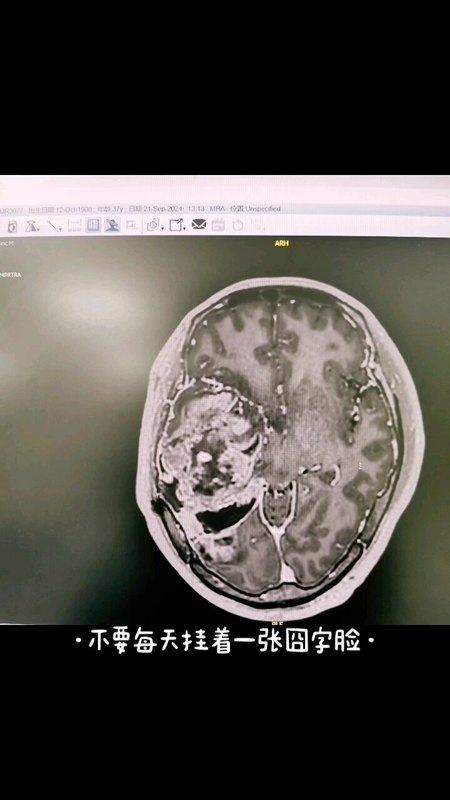

手术切除巨大胶质母细胞瘤,挽救患者生命

孟肖利副主任医师 医科院肿瘤医院 神经外科